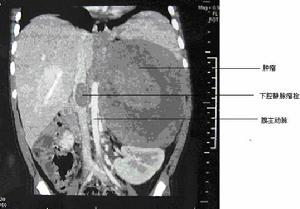

3.影像學檢查經B超、CT、MRI檢查發現膀胱腫瘤或膀胱鏡下肉眼所見或檢病理證實為膀胱腫瘤即可明確診斷。